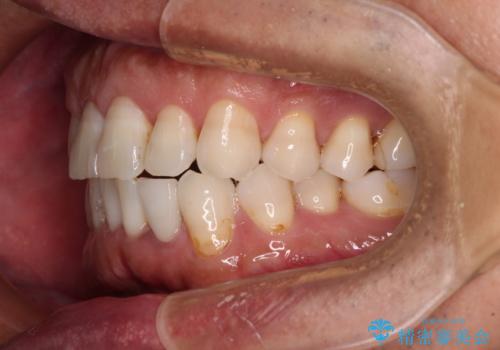

内側にある歯が干渉する 上顎前歯の部分矯正

- 上顎の前歯が内側にあり、下顎のセラミッククラウンと干渉することが気になるとのことで来院された患者様です。

上顎前歯にワイヤー装置を装着し、セラミッククラウンとは干渉しないようにしながら歯列を整えることとしました。

セラミッククラウンとの干渉はすぐに改善され、歯列も整いましたが、一方で、前歯で食事が噛みにくくなり、1年近い治療期間となりました。